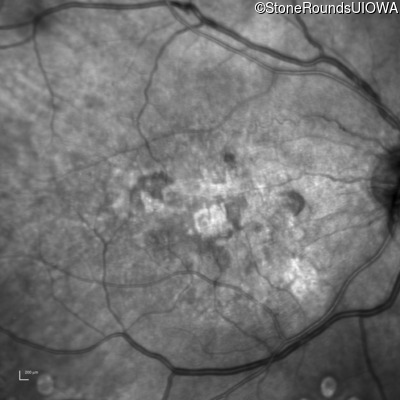

Malattia Leventinese (IIJ)

Malattia Leventinese (IIJ)

This 43 year old woman has experienced a gradual reduction in her central vision for the past 3 years.

| Malattia Leventinese | EFEMP1 | Arg345Trp CGG>TGG | AD |